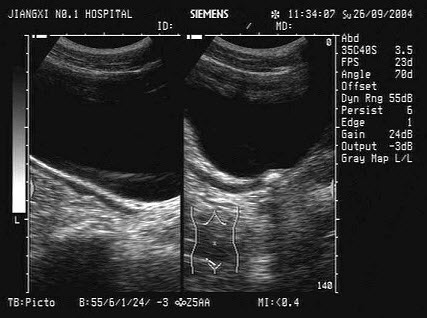

女性,36岁,行常规超声妇科体检。声像图表现如图。血HCG为2258μg/ml。最可能的诊断是()

A.绒癌

B.子宫腺肌瘤

C.早期妊娠

D.子宫肌瘤

E.良性葡萄胎